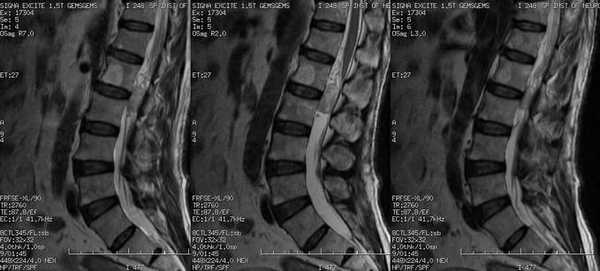

Изображения позвоночника МРТ с миелографией: гемангиома тела 2 поясничного позвонка, опухоль области спинного мозга без ликворного блока

Диагностику проводят по показаниям в качестве дополнения к стандартному магнитно-резонансному сканированию. МРТ разных отделов позвоночника с миелографией предполагает получение Т2-взвешенных изображений (последовательности с градиентными или ускоренными SE), где на фоне ярко окрашенной жидкости виден спинной мозг с корешками.